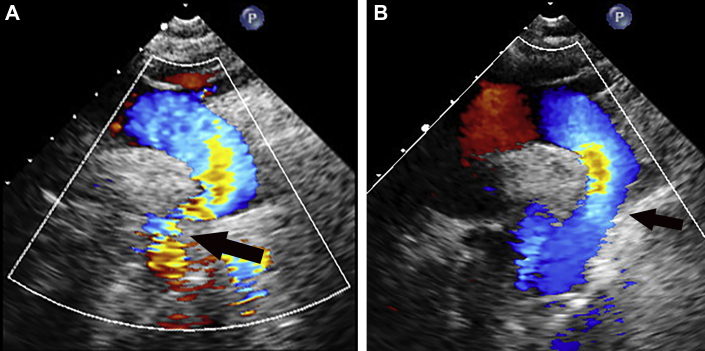

Complete blood count and chemistry assay results were unremarkable. Troponin level was undetectable. Electrocardiography showed normal sinus rhythm without ST-segment changes or T-wave abnormalities. Chest radiography demonstrated cardiomegaly with a mildly tortuous aorta. Echocardiography demonstrated a dilated ascending aorta and transverse arch with increased flow velocity in the descending aorta despite attenuated abdominal aortic pulsations and antegrade diastolic runoff consistent with significant coarctation (Figure 1). Biventricular function was normal.

Figure 1.

Suprasternal Echocardiographic Color Doppler Images Before and After Intervention

(A) Prior to stent placement, the ascending aorta and transverse arch were dilated and aliased color flow across the coarctation site (arrow) with a peak velocity of 3.5 m/s. (B) Flow is significantly improved across the stented area, with a peak velocity of 1.5 m/s.